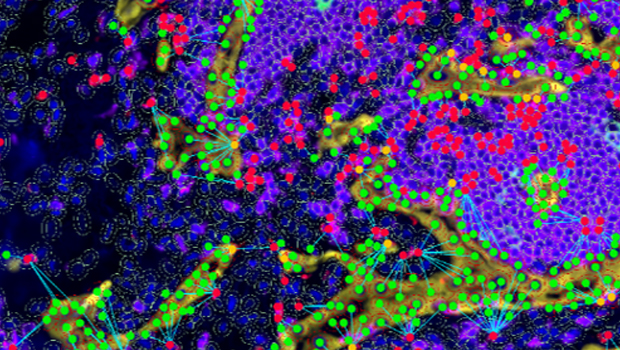

单细胞:准确识别单个细胞的细胞核、细胞质、细胞膜染色区域,提供面积、染色强度、数量及多种形态学数据,包括总细胞及阳性细胞的计数、平均强度、百分比等; 组织结构:基于AI自学习实现特殊组织类型的识别,如三级淋巴结构,提供数量、面积、染色强度、百分比等量化分析数据; 空间分布:特定组织或结构分层划分实现组织微环境的细化分析,提供组织与细胞之间不同形态关系分布及蛋白/mRNA表达的空间分布数据。 |

识别分析区域内每个靶细胞的空间位置,计算两两细胞的距离,可分析某类细胞在一定区间范围内另一靶细胞的分布情况,并给出数据统计直方图。